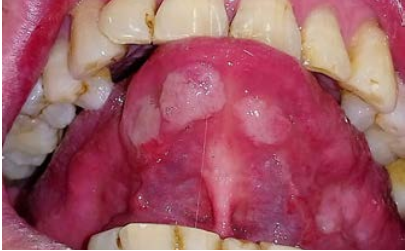

Al examen clínico se pueden observar múltiples lesiones en la cavidad bucal ubicadas en mucosa labial inferior, zona retrocomisural, cara ventral de lengua y tercio posterior de paladar blando y amígdalas, placas blancas de aspecto opalino compatible con pápulas sifilíticas de tres semanas de evolución, dolorosas, con adenopatías submaxilares y occipitales bilaterales positivas e indoloras (Figuras 1 a 4). El diagnóstico presuntivo fue de sífilis secundaria.

Figura 3 Múltiples lesiones blancas nacaradas, elevadas y circunscriptas ubicadas en cara ventral de lengua.